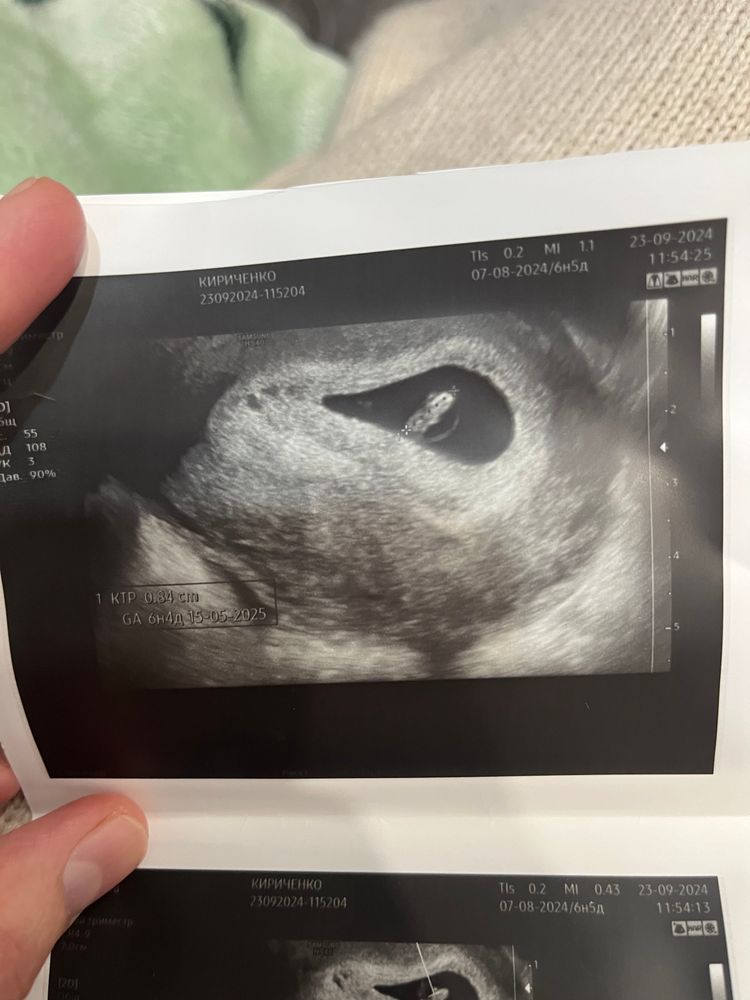

Alisa Y, вот такой вот малыш )) Изображение

Белк@, не видно бугорок. А есть ещё фото?

Белк@, там вроде что то прослеживается, но как будто мальчик. Ножка мешает сильно

Алена, Нашла😄 Не знаю какой из них подойдет 😅все скинула Изображение Изображение Изображение